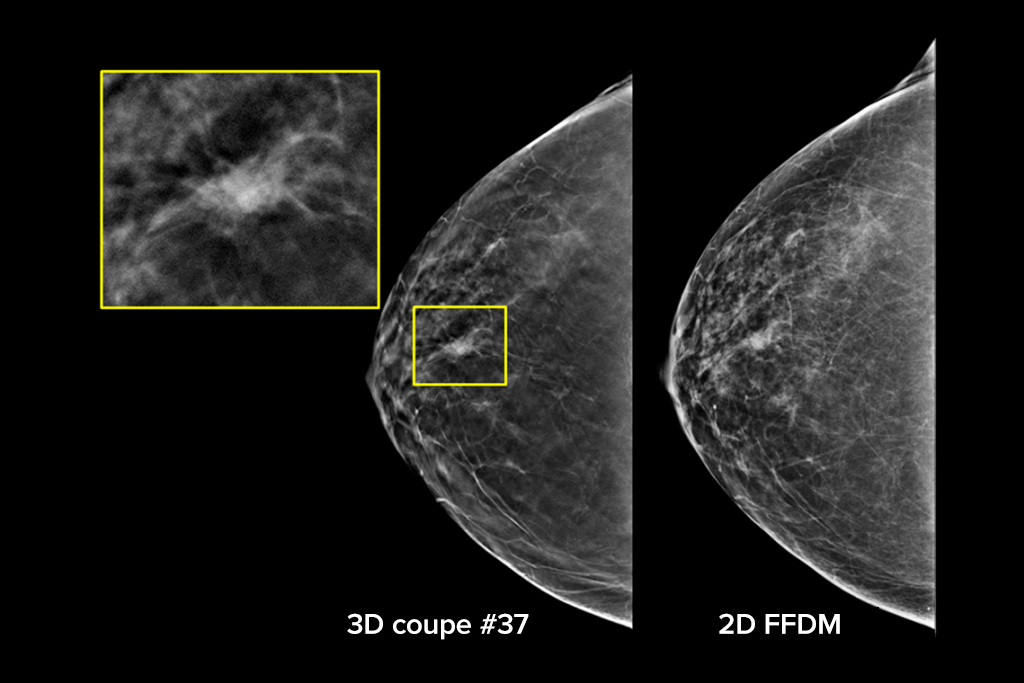

Le système Selenia Dimensions bénéficie de la précision prouvée de notre examen 3D Mammography pour détecter beaucoup plus tôt davantage de cancers invasifs du sein et diminuer les rappels par rapport à la 2D seule.2-6,*

Détectez jusqu’à 65 % de cancers invasifs en plus et réduisez les rappels de 40 % par rapport à la 2D seule.2-4,*

Une plus grande précision pour les femmes présentant des seins denses par rapport à la 2D seule.6